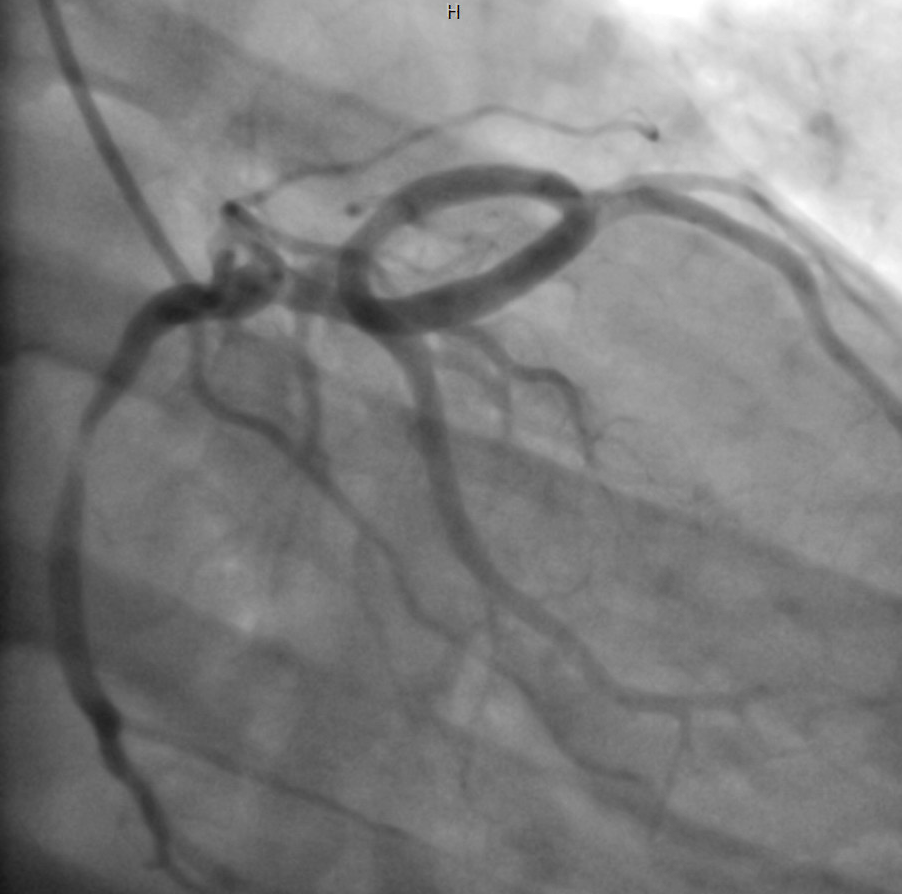

Coronary angiography was performed through right radial approach using 5F TIG catheter. Left coronary sinus contrast injection failed to show any coronary artery origin despite multiple attempts. Right coronary sinus injection showed a coronary artery arising from right coronary cusp as a single trunk which divides into RCA and left system. Left system further divides into LAD and LCX. Mid RCA showed a very tight concentric severe stenosis. Left system was devoid of any significant disease.

Percutaneous Coronary Intervention (PCI) of mid RCA: Common coronary trunk ostium was engaged with a 6F JR4.0 guiding catheter with meticulous care to prevent any ostial injury. Mid RCA lesion crossed with a 0.014¡± BMW wire. Predilated the lesion with 2.5x12mm semi compliant balloon. Stenting of the lesion was done using a DES (3.5x23mm) with final good result. A cardiac CT was done following PCI which confirmed the angiographic findings and found normal subpulmonic non-malignant course of left branch vessel (Lipton's class R II A).